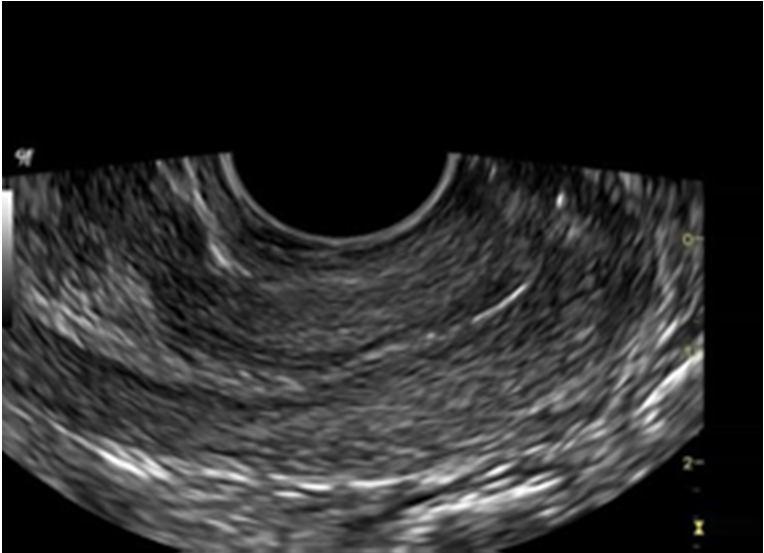

Fig 1. Polycystic ovary syndrome

The dataset is collected from the kaggle. It is the freely available dataset having ultrasound images. The dataset comprises two classes of images - ‘Infected and Non-Infected’. 1,562 images for the infected class and 2,284 images for Non Infected class. For each class, the images are divided into training, testing, and validation sets. The figures show the difference between the two classes. An image with PCOS has a net-like structure which is blood cells grouping or the follicles and the normal ovary

images do not have a net-like structure or have less number of follicles. For the second module, records from the dataset are collected by floating the form. Till now it contains 167 responses. The form contained 23 questions and answers of which will result in various features. The features are age, marital status, body description, no. of kids, menstrual cycle duration, pain during the menstrual cycle, etc. Based on the features of the previous response, the new response gets classified into PCOS and Non - PCOS

Fig 3. PCOS Ultrasound Fig 4. Non-PCOS Ultrasound